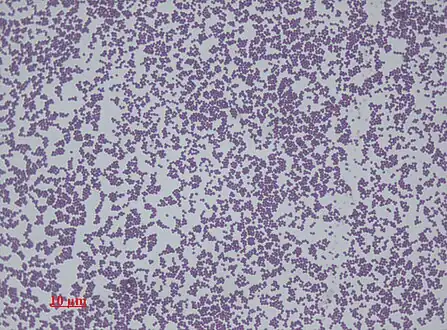

Staphylococcus epidermidis biofilm on titanium substrate Staphylococcus epidermidis, 1000 magnification under bright field microscopy

Staphylococcus epidermidis, 1000 magnification under bright field microscopy

The normal practice of detecting S. epidermidis is by using appearance of colonies on selective media, bacterial morphology by light microscopy, catalase and slide coagulase testing. Zobell agar is useful for the isolation of Staphylococcus epidermidis from marine organisms.[3] On the Baird-Parker agar with egg yolk supplement, colonies appear small and black. Increasingly, techniques such as quantitative PCR are being employed for the rapid detection and identification of Staphylococcus strains.[17][18] Normally, sensitivity to desferrioxamine can also be used to distinguish it from most other staphylococci, except in the case of Staphylococcus hominis, which is also sensitive.[19] In this case, the production of acid from trehalose by S. hominis can be used to tell the two species apart.